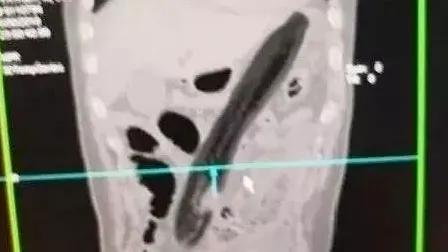

泸州泸县53岁的黄先生自行将直径5.62cm高度5.91cm的啤酒玻璃杯从肛门塞入直肠,弄不出来,随即就诊。接诊医师询问病史,完善CT检查发现玻璃杯滞留直肠内,距离肛门口约6cm,杯口朝下,杯底朝上,下宽上窄,肛门周围组织水肿严重。